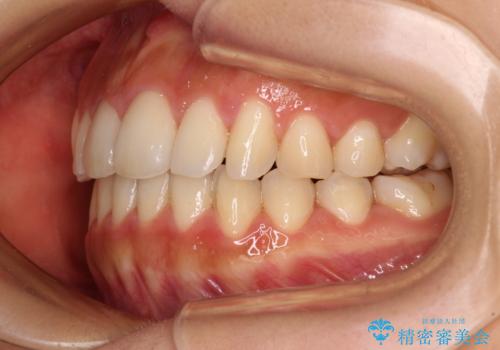

カリエールディスタライザーを併用した、咬み合わせ改善のインビザライン矯正

- 飛び出した前歯と口元の突出感を気にして来院された患者様です。

奥歯の咬み合わせを見ると、上顎が下顎に対して相対的に前方にありました。

口元の突出感を改善するためには、上顎臼歯を後方に移動させた咬み合わせにする必要があります。

インビザライン単体で改善することも可能ですが、達成する可能性が高くないため、カリエールディスタライザーという補助装置を併用して、より確実性を上げることとしました。

奥歯の咬み合わせを改善しながら、並行してインビザラインで歯列を整えることとしました。

カリエールディスタライザーを併用したことで、確実かつ短期間で治療を終えることができました。